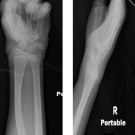

Authors: Helaine G. St. Amant, BA; Alexander Van Speybroeck, MD, MPH; and Mikako Warren, MD

10/31/2018